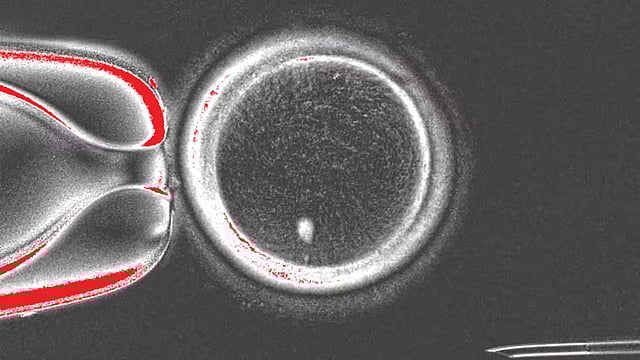

Human Skin cell embryo | मानवी त्वचेच्या पेशींपासून बनवले बीजांड Pudhari File Photo

‘नेचर कम्युनिकेशन्स’ नावाच्या नियतकालिकात प्रकाशित झालेल्या या ‘प्रूफ-ऑफ-कॉन्सेप्ट’ अभ्यासात, संशोधकांनी सामान्य मानवी त्वचेच्या पेशींमधून केंद्रक, म्हणजेच पेशीचा तो भाग ज्यात बहुतेक जनुकीय माहिती असते, वेगळा केला. त्यानंतर हे केंद्रक, ज्याचे केंद्रक काढले आहे, अशा दात्याच्या अंड्यामध्ये (donor egg) प्रत्यारोपित केले. या प्रक्रियेतून संशोधकांनी एकूण 82 कार्यक्षम मानवी अंडपेशी ( immature egg cells) तयार केल्या, ज्यांवर नंतर प्रयोगशाळेत फलन (fertilization) केले गेले. या प्रयोगाचे यश म्हणजे, तयार झालेले अंडे हे त्वचेची पेशी देणार्‍या व्यक्तीसोबत डीएनए सामायिक (DNA shares) करते आणि ते दुसर्‍या व्यक्तीच्या शुक्राणूंनी फलित केले जाऊ शकते.

त्वचेच्या पेशींसारख्या सामान्य मानवी पेशींमध्ये 46 गुणसूत्र असतात. परंतु, लैंगिक पेशींमध्ये (अंड आणि शुक्राणू) याच्या निम्मी, म्हणजेच प्रत्येकी 23 गुणसूत्रे असतात. पोर्टलँडमधील ओरेगॉन हेल्थ अँड सायन्स युनिव्हर्सिटी (OHSU) येथील पथकाने एक अशी पद्धत विकसित केली, ज्यामुळे अतिरिक्त गुणसूत्र काढून टाकली जातात. त्यांनी नैसर्गिक पेशी विभाजनाचे अनुकरण करून 23 गुणसूत्रांचा एक संच बाहेर काढला, ज्यामुळे एक कार्यक्षम अंडपेशी तयार झाली. या प्रक्रियेला संशोधकांनी ‘मायटोमेओसिस‘ असे नाव दिले आहे. अभ्यासादरम्यान तयार झालेल्या अंड्यांपैकी 9% पेक्षा कमी अंडी भ्रूण विकासाच्या ब्लास्टोसिस्ट टप्प्यापर्यंत पोहोचली (फलनानंतरचे पाच किंवा सहा दिवस).